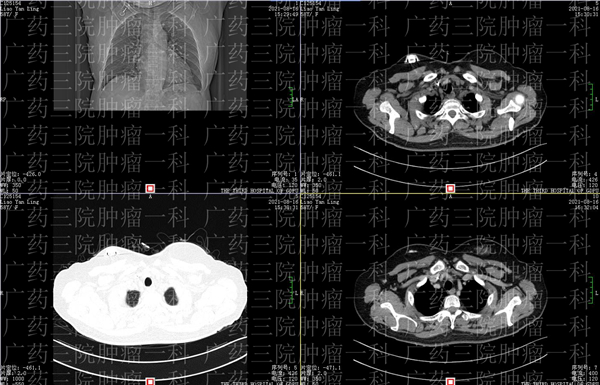

2019 年,廖女士无意间发现,自己的右乳上有一个小小的肿块,但这个肿块真的太小了,仅有 1cmX0. 5cm ,所以当时廖女士并不以为意。但在两年后,今年 2 月份,一次增强 MR 检查提示廖女士,她的双侧乳腺呈不均匀致密型,两年前发现的右乳肿物,可疑恶性,右侧的腋窝也有稍大的淋巴结,医生暂时考虑可能是转移。

于是,在医生的帮助下,廖女士进行了右乳乳腺肿块穿刺活检,病理的结果显示,廖女士右乳肿物的病理,结合免疫组化结果,符合浸润性导管癌。

不仅如此,廖女士右腋窝下淋巴肿块的穿刺物活检里,有大部分区域也符合浸润性癌,基本可以判断,廖女士确诊右乳恶性肿瘤并淋巴结转移。

两年的时间,一个小小的仅 0.5 厘米的小肿块,就变成了癌症,并且已经出现了转移。